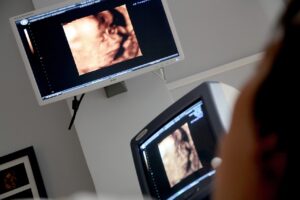

Ultrasound scans are crucial for diagnosing various medical conditions, and Dr Wadhwa Ultrasound CliniQ & Lab provides a full spectrum of services, including 3D/4D ultrasound services in Delhi. These advanced scans are ideal for prenatal assessments, giving expectant parents a detailed glimpse of their baby’s development. For those searching for a USG scan near me in Delhi, our clinic is a convenient choice for residents of Model Town, Ashok Vihar, Mukherjee Nagar, and other nearby areas.

Pregnancy is a delicate journey that requires precise monitoring. At our pregnancy ultrasound clinic in Delhi, we offer high-quality scans to ensure both maternal and foetal well-being. From routine check-ups to detailed anomaly scans, our expert radiologists are here to support you every step of the way. Families from Shalimar Bagh, Hudson Lane, and Rajouri Garden trust us for their pregnancy care needs.

- 3D/4D ultrasound services in Delhi: State-of-the-art imaging for detailed foetal scans.